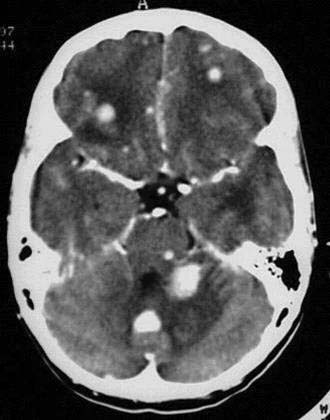

44 jähriger Patientin mit bekanntem malignem Melanom. Patient klagt über

starke Kopfschmerzen.

Multiple

hyperdense KM-aufnehmende Raumforderungen bifrontal und in der linken

Kleinhirnhemisphäre. Hypodense

Areale um die Raumforderungen.

Hirnmetastasen bei bekanntem malignen Melanom mit perifokalen Ödemen.